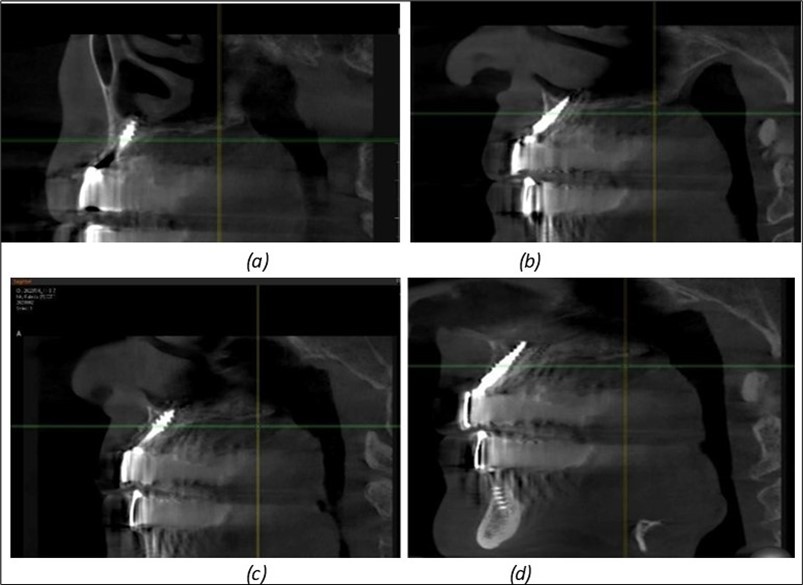

Figure 9.Implants in the pterygoid plateau area: (a) TPG implant fixed in the maxillary-sphenoid junction area, quadrant 1; (b) TPG implant fixed in the maxillary-sphenoid junction area, quadrant 2.

Implants in the pterygoid plateau area: (a) TPG implant fixed in the maxillary-sphenoid junction area, quadrant 1; (b) TPG implant fixed in the maxillary-sphenoid junction area, quadrant 2.